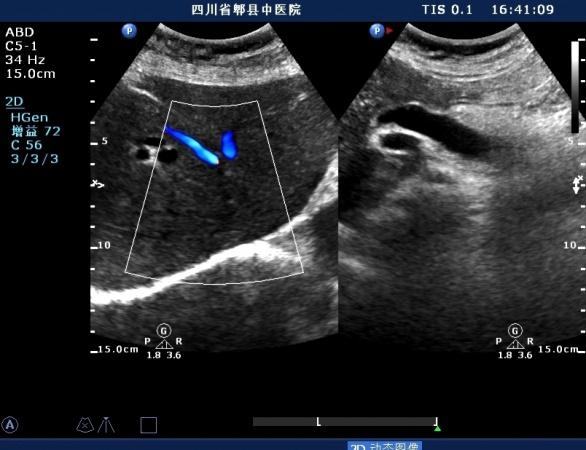

超声如图:胆总管及肝内胆管扩张,呈“平行管征”,胆总管胰腺段可见疏松强回声团堆积,后方可见淡淡声影,左肝外叶胆管内亦可见数个强回声团堆积,后方伴声影。 肝脏及胆总管

扩张的左肝内胆管

扩张的右肝内胆管